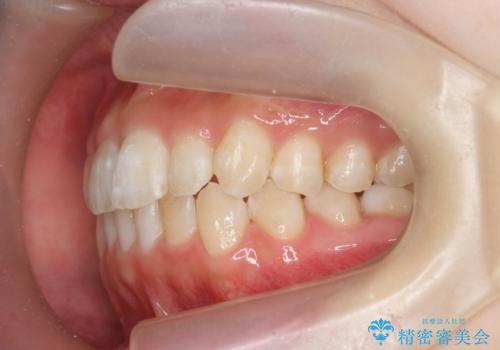

前歯のねじれを治したい マウスピース矯正治療

- 前歯のねじれを改善し、きれいな歯並びにしたい!と矯正治療を希望され来院されました。

マウスピース矯正システム、インビザラインのシミュレーションを用いて最終的な歯の位置をしっかりと確認したのち、きれいな歯並びとなるようマウスピース矯正治療を開始します。

ねじれとともに突き出たように見えていた前歯も見た目が大きく改善し、喜んでいただくことができました。